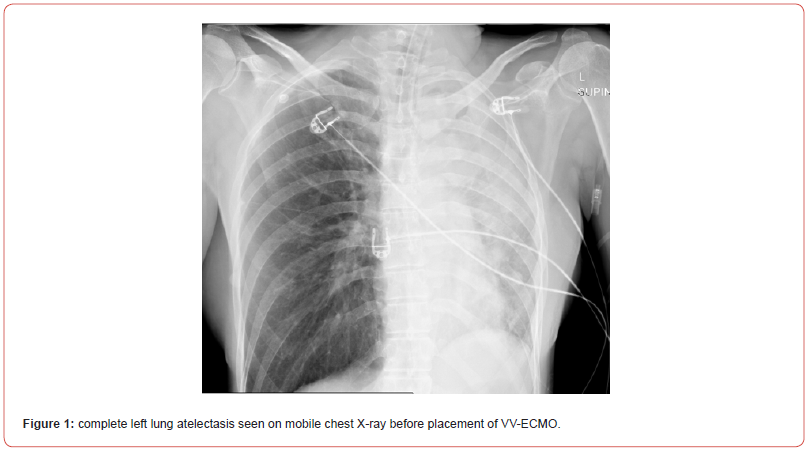

Shortly after, the situation escalated rapidly; the patient experienced a sudden desaturation to 70% and was emergently intubated. Mobile chest x-ray revealed complete atelectasis of the left lung (figure 1). Immediate bronchoscopy showed large amount of blood and blood clots in the left main bronchus and despite ongoing suctioning, the left lung did not re-inflate and the patient remained severely hypoxic. Few hours later a venous-venous extra-corporal membrane oxygenation (VV-ECMO) was emergently placed due to refractory hypoxemia (figure 2). In the following days, the patient’s lungs did not re-inflate despite multiple bronchoscopies performed due to ongoing bleeding that filled the airways with blood clots up to the upper trachea (figure 3). Tracheostomy was placed but blood clots filled also the tracheostomy tube that needed to be capped to prevent ongoing blood loss. The patient was treated with full VV-ECMO support, disconnected from the ventilator due to zero tidal volume secondary to the blocked trachea, and in the following weeks developed septic shock and acute renal failure requiring hemodialysis. In attempt to stop the ongoing bronchial bleeding the patient was transferred almost daily to the radiation oncology unit to receive radiation while on VV-ECMO (20 Gy in 10 fractions over 2 weeks) to the proximal tracheobronchial tree [4]. During and after completion of the radiation, multiple bronchoscopies aimed at controlling bronchial bleeding and clearing airway obstructions were conducted, unfortunately unsuccessfully.